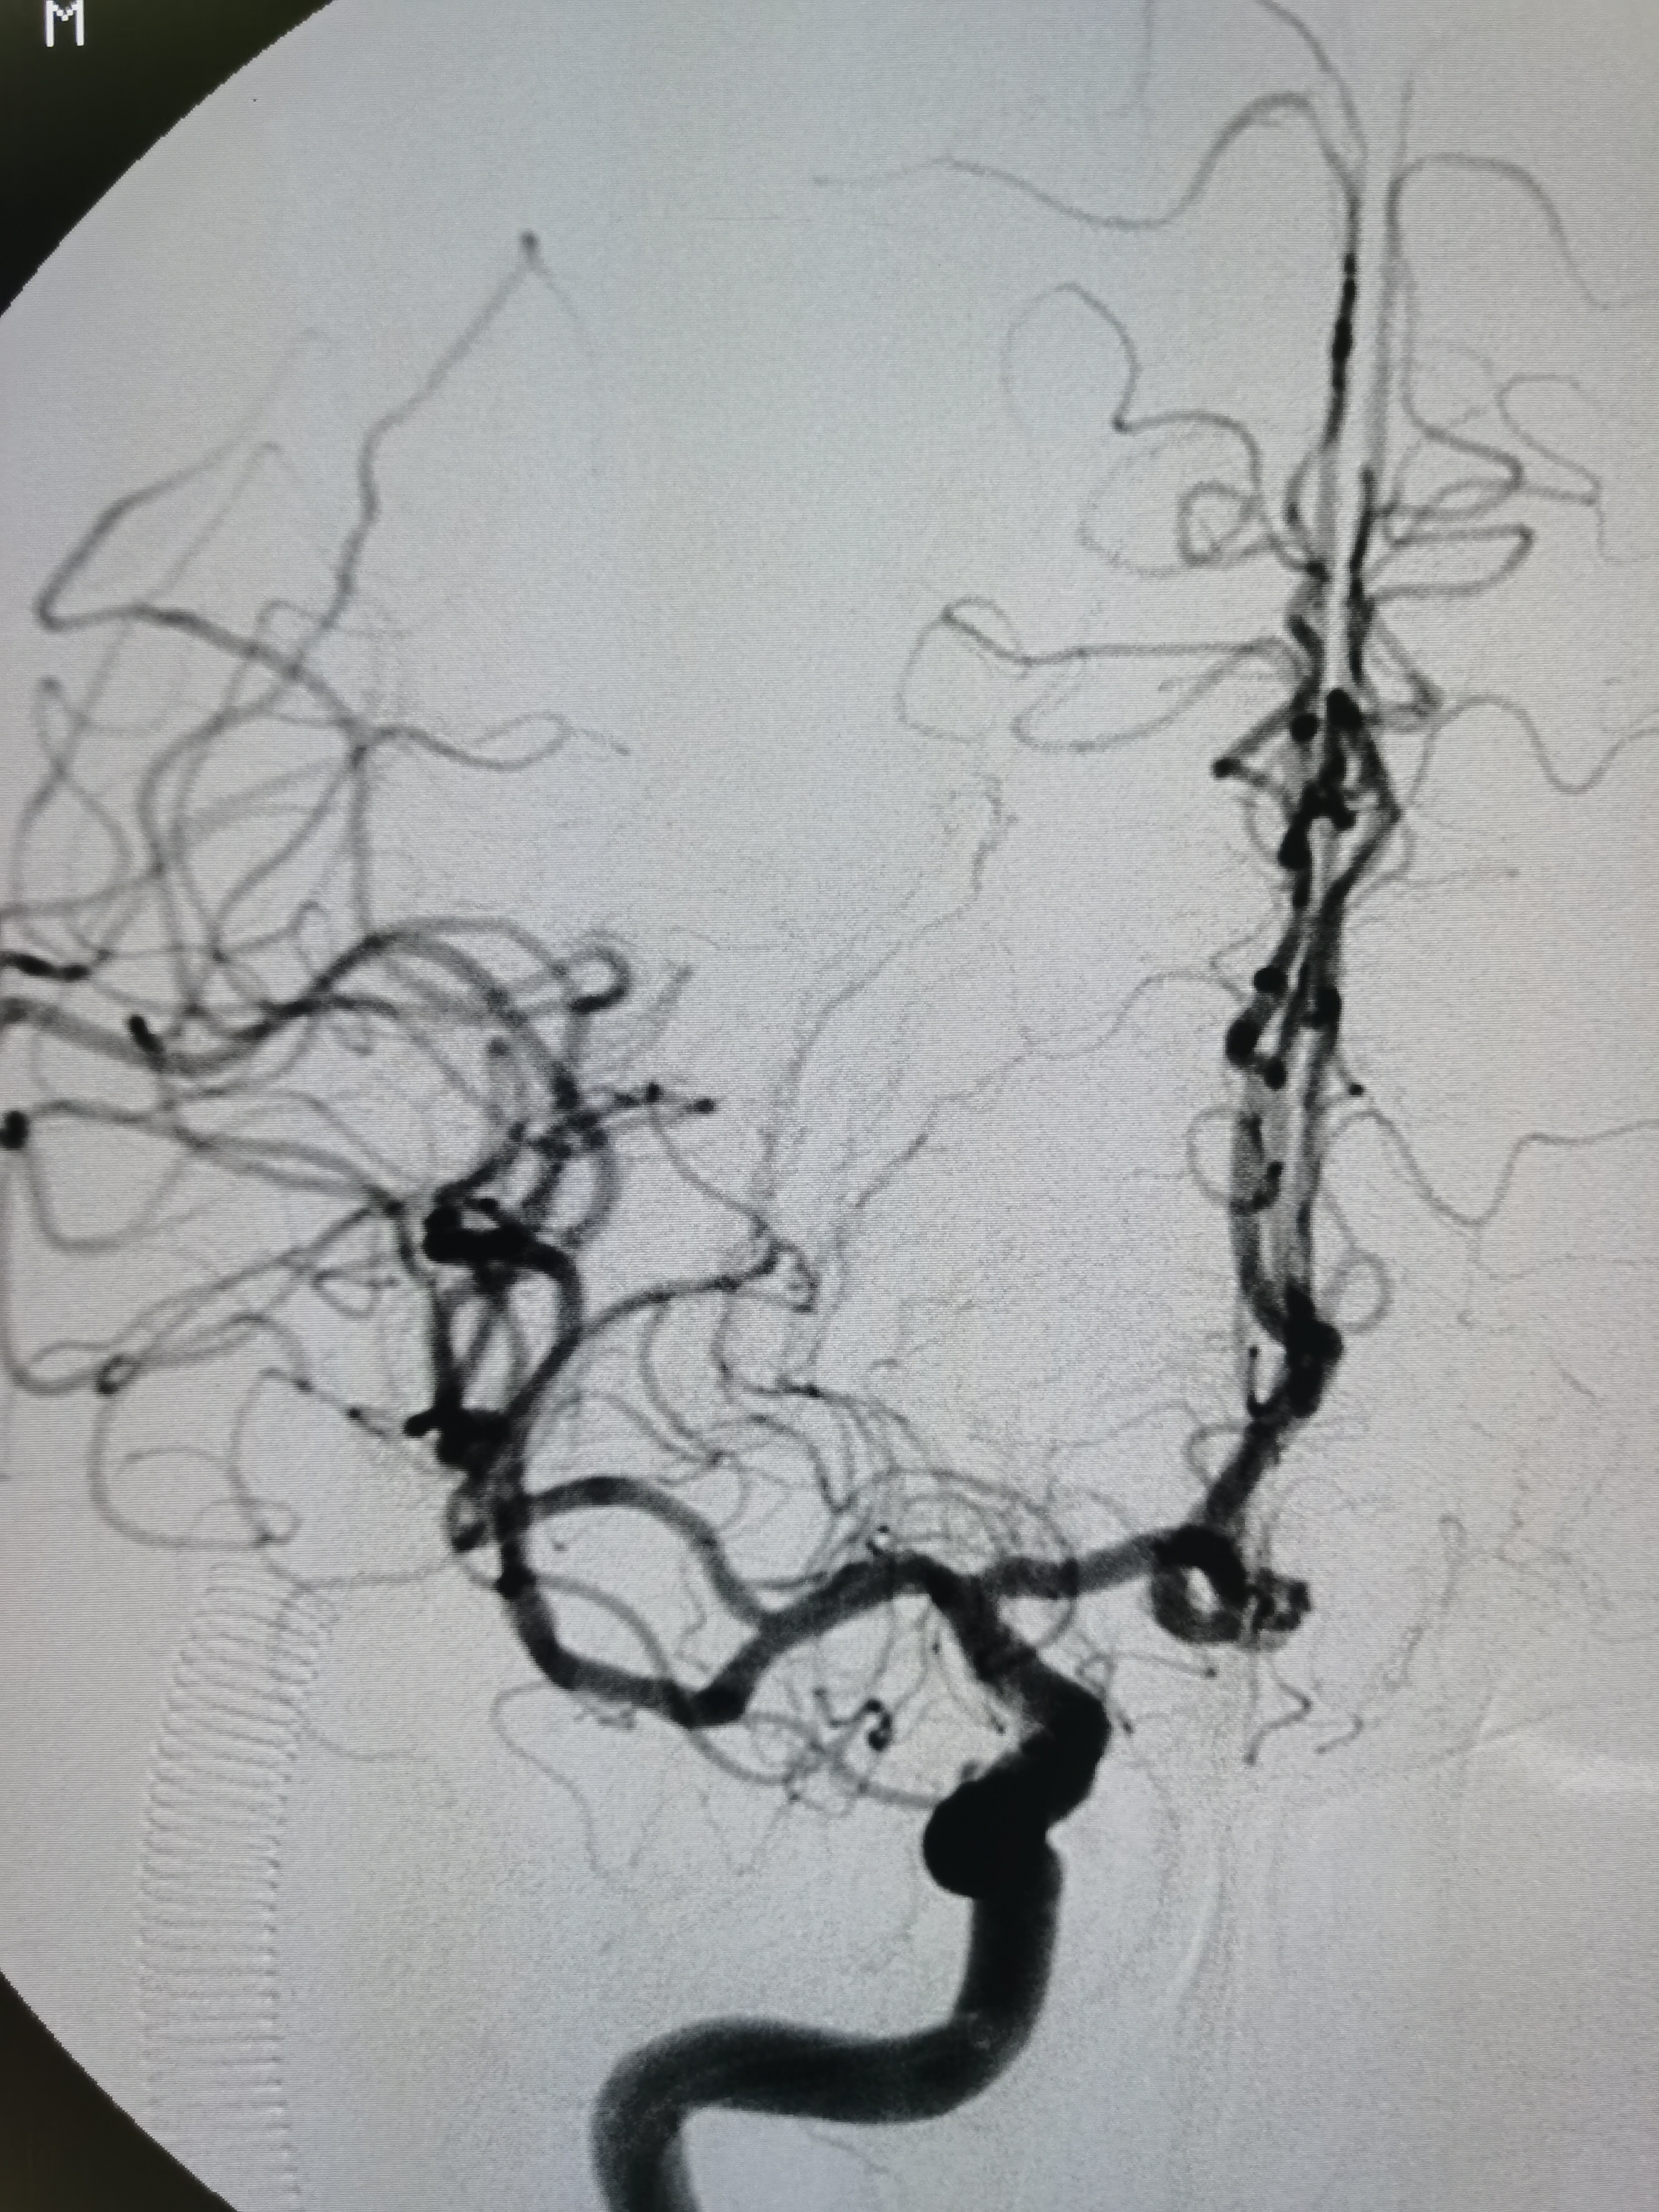

颅内侧位显影可。

右侧大脑中动脉M1段重度狭窄。

右侧大脑中动脉M1段重度狭窄,病变处存在豆纹动脉。

患者右侧大脑中动脉M1段重度狭窄,病变处存在豆纹动脉分支,具备介入治疗指征,手术风险在于血管夹层,破裂及穿支闭塞可能,向患者家属详细交代病情及风险后,家属积极要求介入治疗。拟行右侧大脑中动脉球囊扩张备支架成形术。

正位造影见狭窄解除,颅内血流通畅。